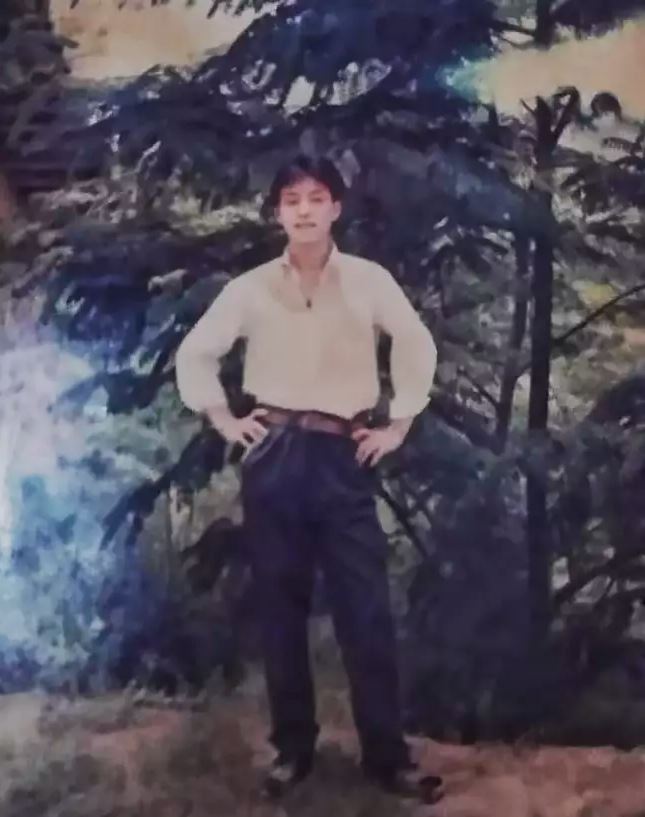

Ο Li είχε διαγνωσθεί με αγκυλοποιητική σπονδυλοαρθρίτιδα το 1991 σε νεαρή ηλικία 18 ετών. Από την διάγνωση του και μετά ο ιδιος «δίπλωνε» ολοένα και περισσότερο με το πέρασμα του χρόνου. Η οικογενεια του δεν είχε την οικονομική δυνατότητα για να του προσφέρουν την κατάλληλη ιατρική περίθαλψη.